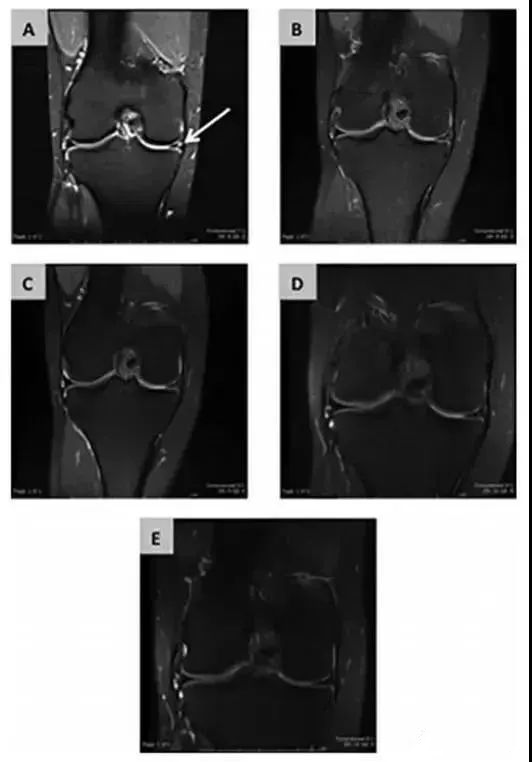

2016年英國布里斯托爾大學對5例無血管半月板損傷患者進行干細胞臨床應用。科研人員將自體骨髓MSCs接種在膠原包被的支架上,MSCs-膠原-支架被移植到5例患者的半月板損傷處。

追蹤隨訪24個月后,發現上述患者癥狀均得到顯著性改善,其中3例癥狀消失,半月板損傷徹底治愈。

(圖a為手術前;圖b術后3個月;圖c術后6個月;圖d術后12個月;圖e術后24個月)